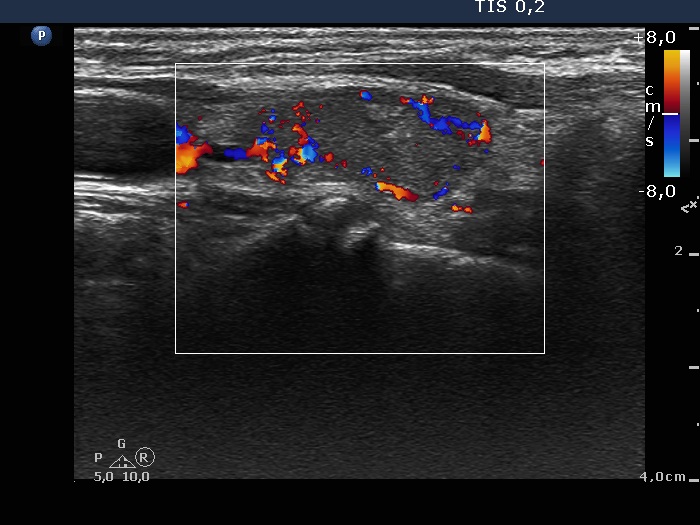

Right lobe, longitudinal scan

Left lobe, longitudinal scan, color Doppler mode. The less hypoechoic mass is avascular.